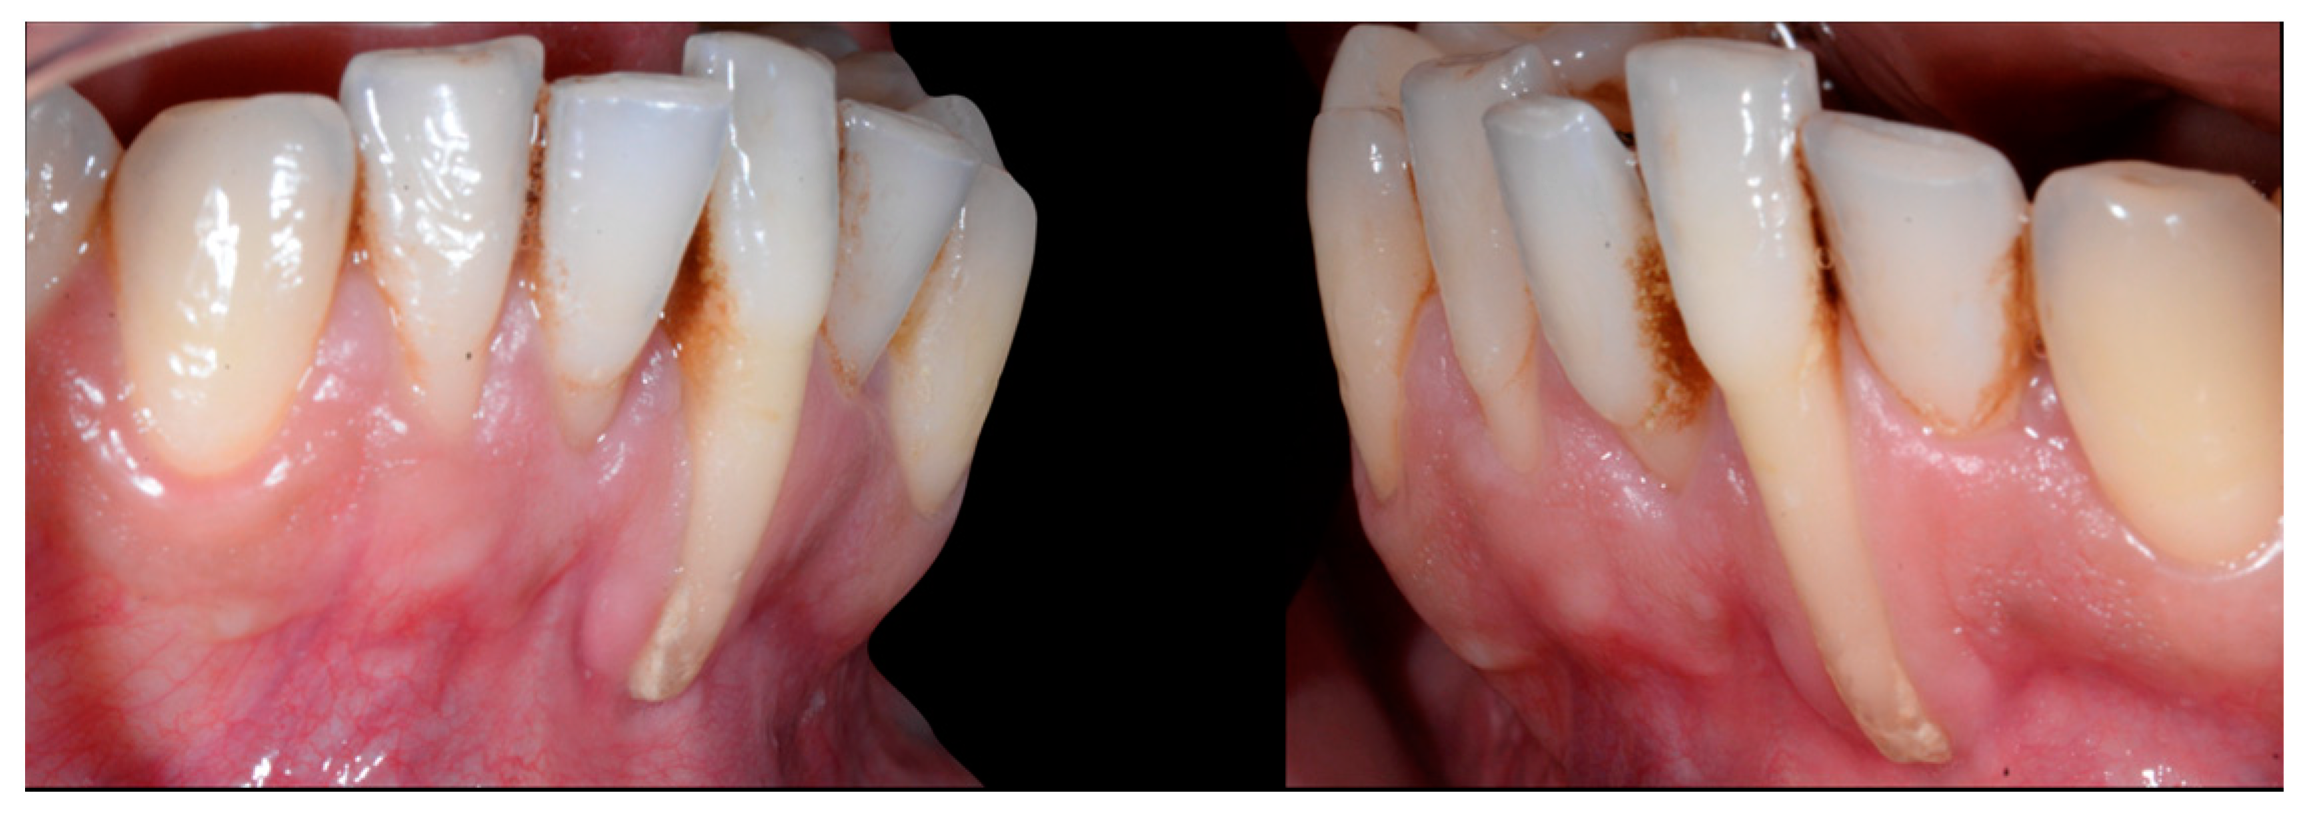

A 22-year-old female patient in good health had a consultation because she was concerned about the “root prominence” of tooth 41. She wore a mandibular retainer wire when she was 16 years old at the end of her orthodontic treatment. She has good oral hygiene, despite the presence of tartar between 31 and 41, and a right and left Class I with a slight deviation of the midlines (Figure 1).

Early wire syndrome. Frontal and lateral views.

In Figure 2, the following can be observed: a difference in gingival margin height between 41 and 31, a difference in height of the incisal edges of 41 compared to the adjacent teeth, and the onset of gingival recession on 41 associated with the visibility of a vestibular arch corresponding to its root.

In the lateral view (Figure 3), the prominence of the root of 41 was confirmed.

Early wire syndrome. Lateral view.

Occlusal views (Figure 4) confirmed the presence of a mandibular retainer which appears intact, without fracture or debonding, along its entire length. In addition, the vestibular surface of 41 appeared to have a difference in visibility from the adjacent teeth. Based on these clinical findings, wire syndrome starting on tooth 41, called the “X-effect” type, was suspected.